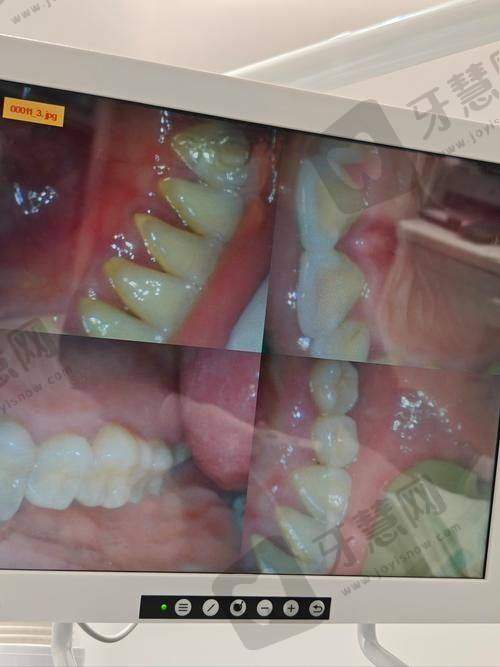

末尾提醒大家:牙贴面是“不可逆”的美牙项目(磨掉的牙釉质不能再生),一定要选正规机构和有经验的医生,别为了低价冒险。如果还纠结“自己适合哪种贴面”,可以点击下方“在线询问”,发送你的牙齿照片和预算,我帮你推荐附近靠谱的机构和医生,还能申请“免费口腔检查”名额哦!